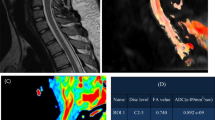

The bias, motion, inhomogeneity and, eddy-current corrections were performed with Spinal Cord ToolBox (SCT, https://github.com/neuropoly/spinalcordtoolbox) and Fsleyes (https://pypi.org/project/fsleyes/) software packages. Regions of interest (ROIs) were obtained after automatically identifying spinal cord segments and segmenting the spinal cord through SCT software packages. The dMRI parameters were included the DTI-based fractional anisotropy (FA), mean diffusivity (MD), axial diffusivity (AD), radial diffusivity (RD), DKI-based mean kurtosis (MK), axial kurtosis (AK), radial kurtosis (RK), and NODDI-based isotropic volume fraction (ISOVF), orientation division index (ODI), neural density index (NDI), and anisotropic water fraction (AWF). The automatic segmentation results and the colour maps of different dMRI variables are illustrated in Fig. 2.

Automatic segmentation results and different dMRI variable colour maps based on sagittal T2WI and transverse T2*MEDIC. This patient was diagnosed with CSM due to C5–C6 cervical disc herniation compressing the spinal cord. The first row is the result of automatic spinal cord segmentation on T2WI images through SCT software and the ROI obtained based on automatic segmentation of transverse T2*MEDIC images. Rows 2-4 represent the colour maps of different DTI, DKI, and NODDI variables, respectively